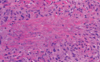

Darkly pigmented, variegated lesions distributed primarily on the trunk and non-sun-exposed skin. These moles feature a combination of architectural disorder (rete-to-rete bridging of melanocytes) and cytologic atypia (melanocytes with large atypical nuclei). These patients are at an increased risk of developing melanoma.

(image displays bridging of rete ridges and melanocytes with cytological atypia, curved arrows)

Keratinocytic neoplasms that develop in sun-damaged skin, commonly on the face or backs of hands. The basal keratinocytes of the stratum spongiosum display significant atypia, as well as hyperkeratosis and parakeratosis. This lesion is a precursor to SCC.

(image displays parakeratosis)

(image displays cytologic atypia of basal keratinocytes)